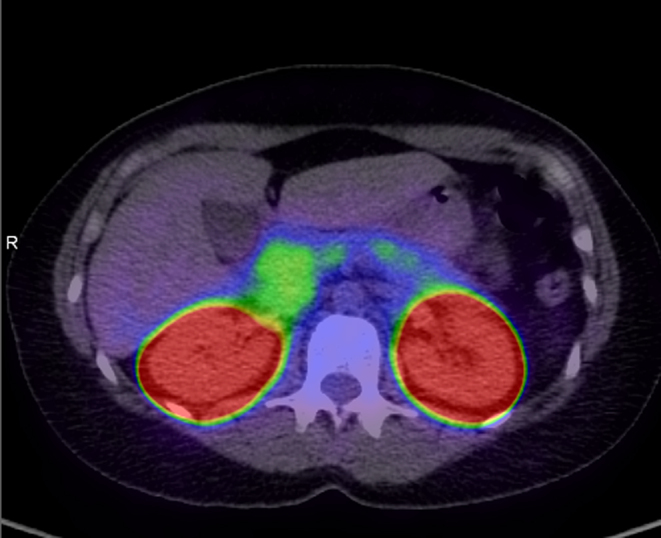

Summary: Congenital hyperinsulinism is the leading cause of persistent hypoglycaemia in infants and children; however, it is uncommon to be diagnosed in adulthood. We describe the cases of two sisters who presented with hyperinsulinaemic hypoglycaemia aged 47 and 57 years old, who were subsequently diagnosed with compound heterozygous likely pathogenic variants in the ABCC8 gene, a known cause of monogenic congenital hyperinsulinism. We discuss the typical presenting features, investigation findings, and treatment strategies for patients with this condition.

Learning points: Congenital hyperinsulinism is a rare cause of hyperinsulinaemic hypoglycaemia diagnosed in adulthood. Clinical presentation is similar to an insulinoma, and imaging modalities may assist in differentiation. There are minimal medical therapies currently available for patients non-responsive to diazoxide (such as those with ABCC8 and KCNJ11 variants). Continuous glucose monitoring can be helpful in giving patients autonomy in managing their disease, as well as relieving anxiety and fear associated with hypoglycaemia.